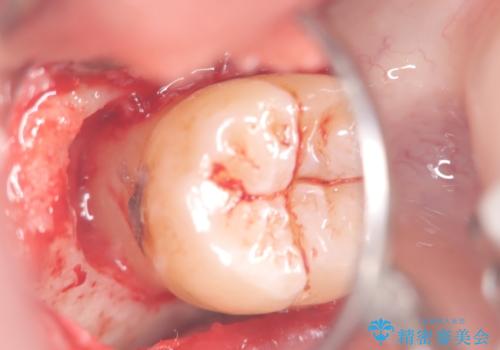

来院時、右下7遠心9mm、舌側6mmと深い歯周ポケットを認めました。

遠心から舌側、唇側に及ぶ深い垂直的骨欠損も認めたため、歯科衛生士による歯周基本治療の後、歯周外科(再生療法)を行いました。